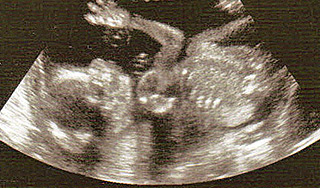

Эмбрионы могут наделить правами человека15 августа 2012, среда, 20:17 – БРЯНСК.RU | Комментарии: 0

| Версия для печати Депутат Законодательного собрания Петербурга Виталий Милонов готовит для парламентариев проект документа, присваивающий эмбриону человека статус гражданина, и, соответственно, запрещающий аборты, которые будут приравнены к убийству. "Мы должны прояснить, что использовать понятие "эмбрион" нельзя. У него есть правоспособность, которая является основой правового государства. Люди не всегда здоровые, веселые, спортивные гимнасты. Некоторые не дышат, находятся в коме и так далее. Но они тоже люди! Почему тогда мы говорим об абортах как о некой косметической операции? Ребенок еще ничего не совершил, а его уже убивают", – приводит "Интерфакс" слова Милонова. По его словам, он внесет свой проект постановления депутатам в сентябре, после теоретического заключения. Как отметил Милонов, инициатива касается правоспособности человека на разных этапах жизни. "Я же не вношу сейчас изменение – полностью запретить аборт. Нет. Просто прошу людей отталкиваться не от лукавых, подменных понятий, а от истинных понятий. Это право общества определять – разрешить убийство ребенка, или не разрешить", – сказал Милонов. Как передает РБК, статус гражданина, по мнению депутата, следует придавать эмбриону человека с момента зачатия или с фиксации сердцебиения. В свою очередь первый заместитель председателя комитета Госдумы по вопросам семьи, женщин и детей, член "Единой России" Ольга Баталина считает, что ответственности может быть введена только в случае криминальных абортов, пишет "Коммерсантъ". "Очень много случаев, когда аборт делается по медицинским показаниям, поэтому пытаться рубить с плеча – так не получится. Жизненных ситуаций очень много, и другой важный аспект темы – это вопрос криминальных абортов. Здесь я согласна – жесткость и принципиальность подхода в искоренения этого явления должна быть и у государства на всех уровнях, и у общества", – заявила она. Ранее председатель отдела по делам молодежи Санкт-Петербургской епархии, иерей Алексей Галкин предложил ввести уголовную ответственность за аборты. Поводом для его предложения стали найденные в июле в Свердловской области бочки с человеческими эмбрионами. Источник: